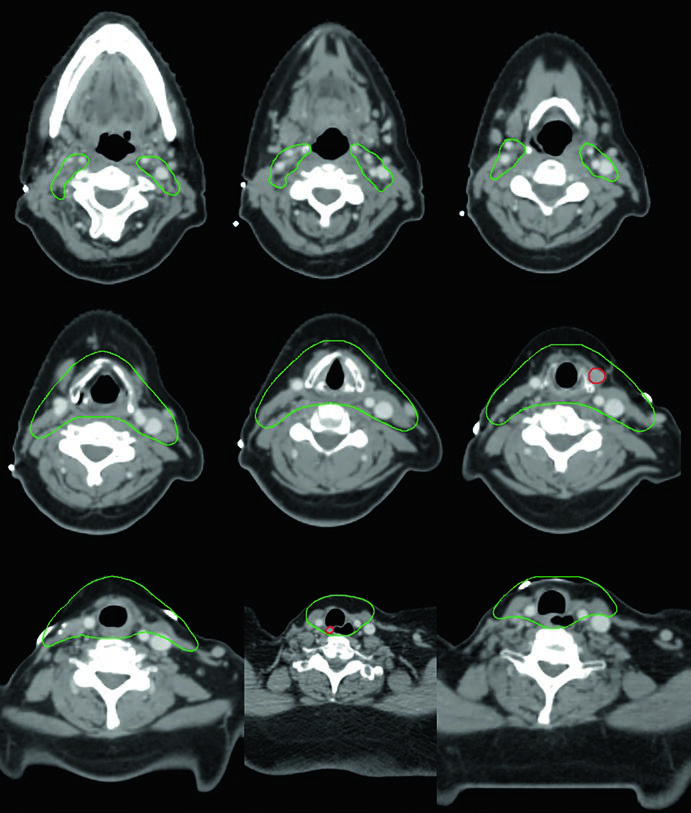

Caso 5 — Câncer pouco diferenciado, fenótipo folicular (Fig. 9.5): Mulher de 69 anos com câncer de tireoide pouco diferenciado de fenótipo folicular, aderido a traqueia e esôfago, submetida a ressecção e iodo radioativo, que recorreu com massa paratraqueal direita invadindo a traqueia. Após nova ressecção e esvaziamento cervical, recebeu quimiorradiação adjuvante. O CTV60 Gy (verde) cobre o compartimento central e o mediastino superior. O tratamento do pescoço lateral foi omitido, dada a alta probabilidade de recorrência no compartimento central — a dose e o risco foram priorizados onde o benefício clínico era máximo.

A decisão de omitir o pescoço lateral não é trivial. Ela pressupõe que o risco de recorrência lateral é suficientemente baixo para que a redução de toxicidade justifique a ausência de cobertura. No cenário deste caso — doença central recorrente com esvaziamento cervical recente e sem linfonodos laterais comprometidos — a omissão é razoável e alinhada com o princípio de individualização do tratamento. Omitir o pescoço lateral reduz significativamente o volume irradiado, com benefício direto na preservação da função de deglutição e redução de xerostomia.